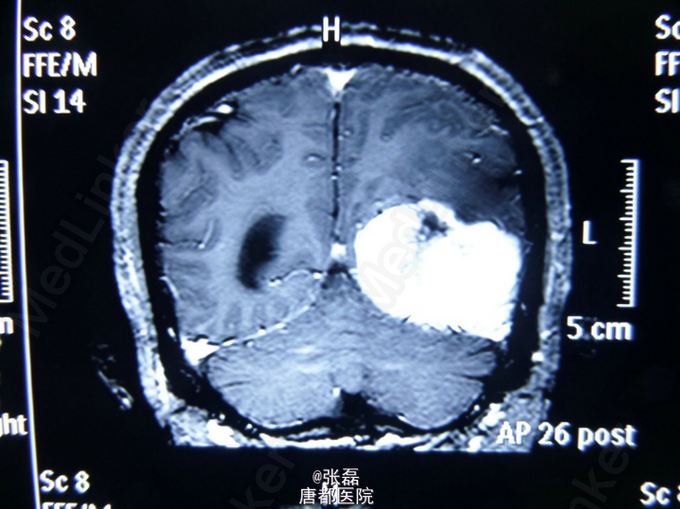

患者男,67岁,自诉头疼3月,伴有癫痫发作。